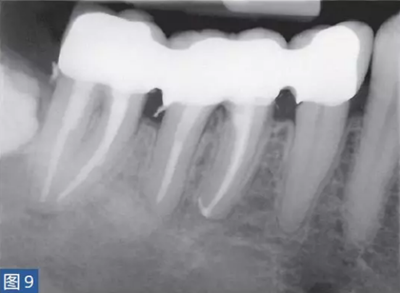

圖9:47 牙齒AAA。根管治療后?;颊咴谄浼彝パ泪t(yī)處做臨時(shí)義齒修復(fù)12 個(gè)月后的檢查。